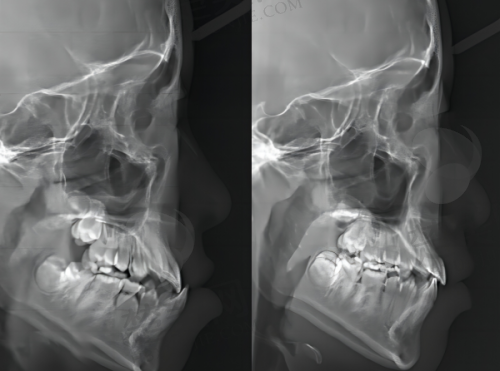

从技术层面来看,龙岩雅致口腔门诊部拥有强大的技术实力。采用数字化3D诊疗设备,支持即拔即种种植技术,为患者提供更精细、效率高的治疗方案。医生团队技术不错,例如刘清华医生是特约正畸医生,擅长青少年、成人各类骨性错颌畸形固定矫正、隐形矫正以及儿童口腔早期矫正;陈东斌医生擅长口腔颌面外科牙槽骨各类复杂种植外科手术等。在设备方面,精良的数字化3D诊疗设备为诊断和治疗提供了有力支持,能够更正确地了解患者口腔状况,制定个性化的治疗方案。

种植牙项目是该门诊部的一大特色。它支持多种种植牙技术,如all - on - 4种植、穿颧穿翼技术、微创即刻种植、all - on - 4即刻负重等。采用数字化3D诊疗设备,医生可以更精细地了解患者牙槽骨的情况,为患者制定更合适的种植方案。在种植过程中,医生经验多,像陈东斌医生擅长口腔颌面外科牙槽骨各类复杂种植外科手术,陈牙斌医生擅长普通种植牙、高难度的all - on - 4种植技术、穿颧穿翼种植。这些医生能够熟练操作各种种植技术,确保种植手术的顺利进行。而且,门诊部使用的种植牙品牌多样,有韩国奥齿泰、瑞士士卓曼ITI、德国HT、瑞士诺贝尔nobel等,患者可以根据自己的需求和经济状况进行选择。